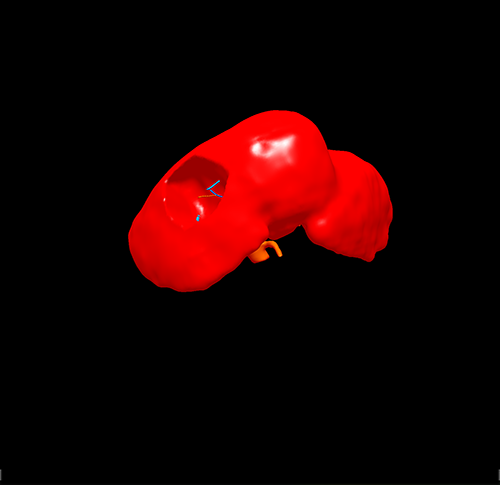

右肝肝癌---右肝肿瘤切除